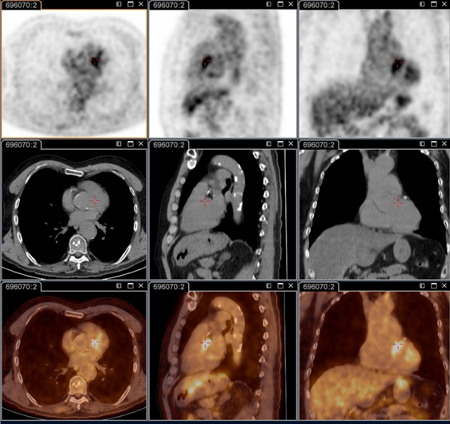

Endocardite por febre Q diagnosticada na PET: PET/TC com 18-fluordesoxiglucose. Neste paciente assintomático com história de valva cardíaca e sorologia elevada, a PET permitiu diagnosticar endocardite aórtica na valva nativa com aneurismas micóticos da aorta torácica e lombar

Institut Hospitalo-Universitaire Méditerranée Infection (obtido consentimento do paciente)

Aneurisma micótico na aorta torácica da febre Q diagnosticado na PET: PET/TC com 18-fluordesoxiglucose. Neste paciente assintomático com história de valva cardíaca e sorologia elevada, a PET permitiu diagnosticar endocardite aórtica na valva nativa com aneurismas micóticos da aorta torácica e lombar